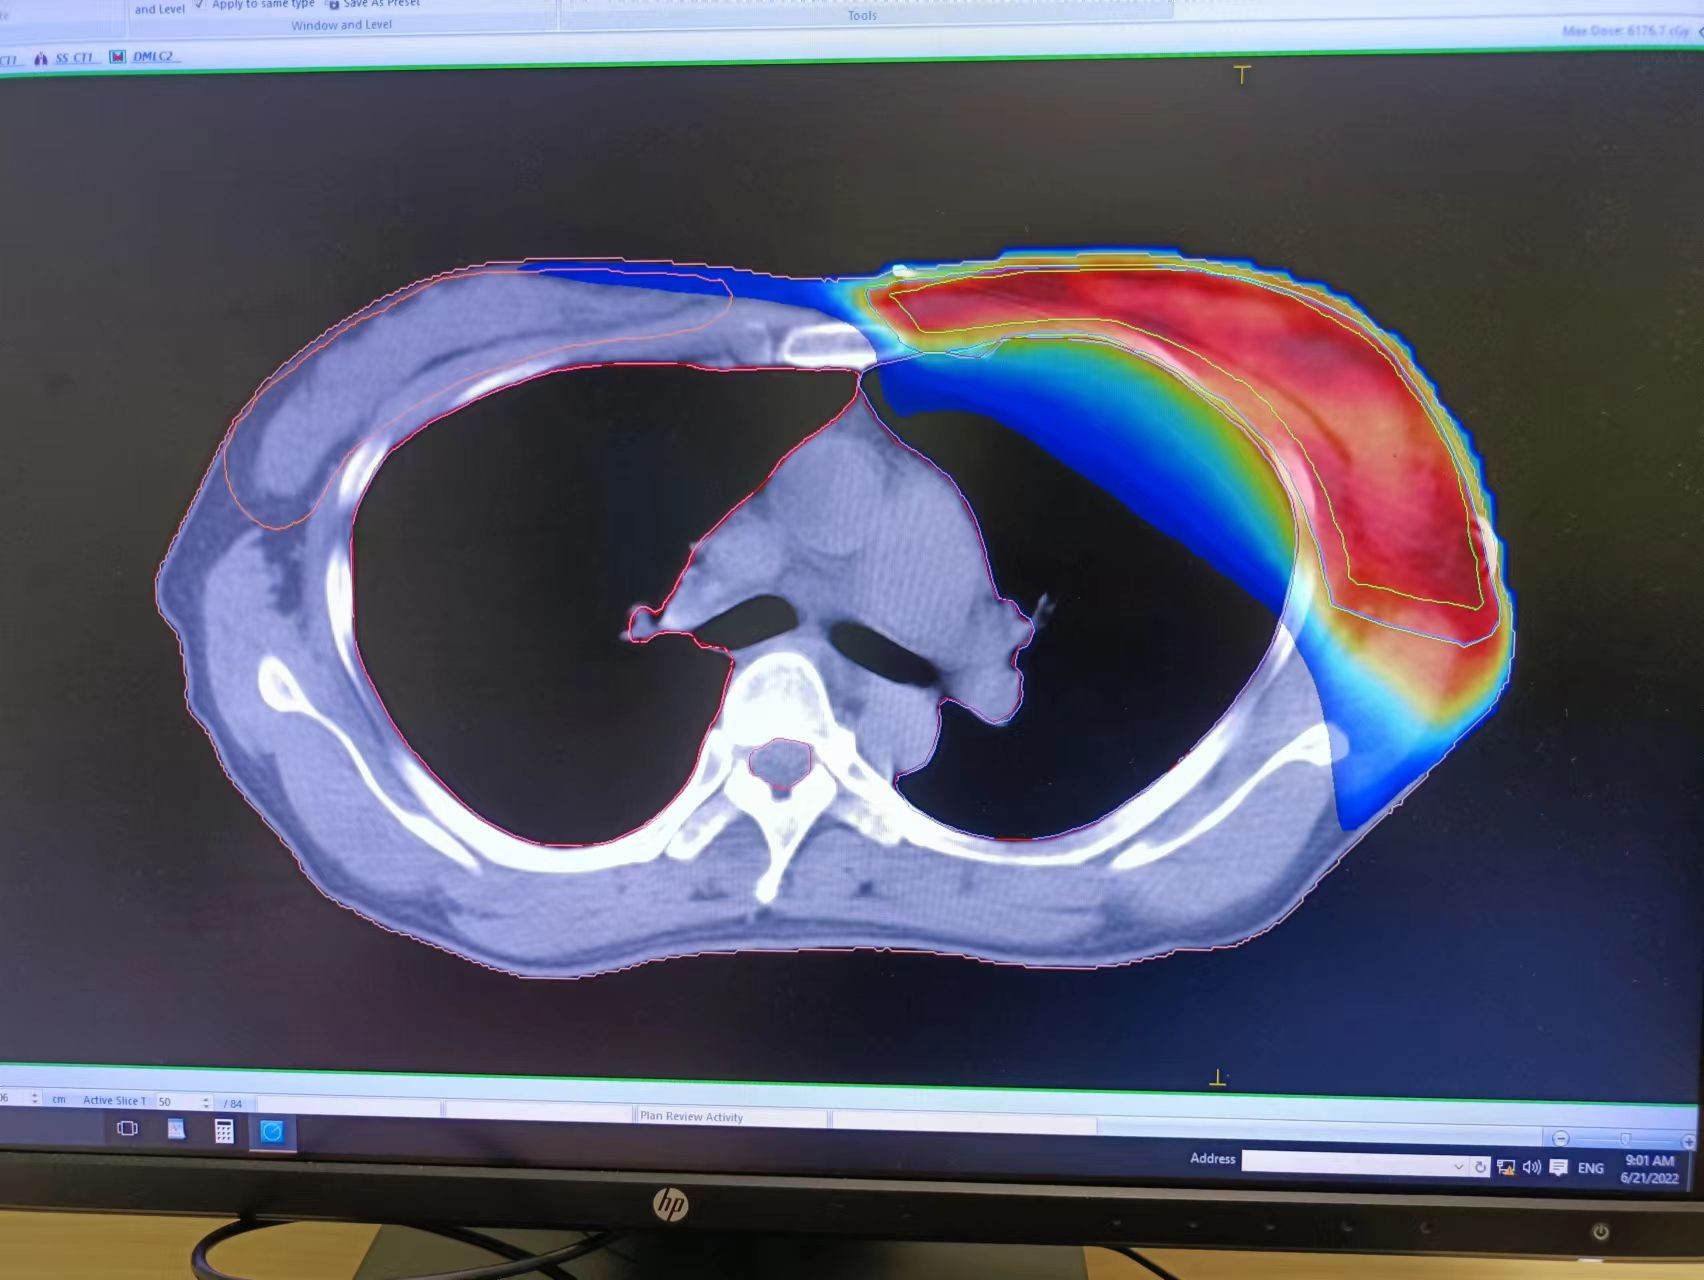

精准放疗是高能射线在3D图像引导下的精确放疗, 它通过CT定位,精准找到病灶,就像“巡航导弹”一样瞄准乳房本身、乳房切除术后的胸腔壁和(或)周围淋巴结,通过精准定位和精确的剂量计算,将放射治疗集中在病变靶区内,以高精度、高剂量、高疗效、低损伤以“清除”那些预谋在未来某天卷土重来的癌细胞;相比普通放疗或常规放疗,它对靶区内的放射剂量更高,周边的正常组织的损伤更小,不良反应更低。

经多方打听,沈小姐得知慈林医院的放疗设备是近两年从瑞典进口的医科达直线加速器,设备非常不错,医生也全是来自大三甲专科肿瘤医院,不但可以进行精准放疗,还可以根据病情选择三维适形放疗、调强放疗或是容积旋转调强放疗,于是最终决定来慈林肿瘤中心进行就诊放疗。

慈林医院放疗科的医科达Synergy直线加速器是世界上较先进的精确放疗设备,包含一台医科达Synergy直线加速器、Synergy XVI在线图像引导系统、IVIEWGT实时射野成像系统、MOSAIQ放射治疗系统、主动呼吸控制系统(ABC)、Monaco放射治疗计划系统和调强治疗计划验证系统。特别是其160片、厚度为5mm的多叶光栅(MLC),完全胜任常规放疗、普通三维适形放疗(3DCRT) 、容积调强、三维适形调强放疗(IMRT),更适合在3D、4D图像引导下的精确放疗(IGRT)等。 备注:因肿瘤病情复杂,可添加拔打0574-63995898或17788539772,咨询医师